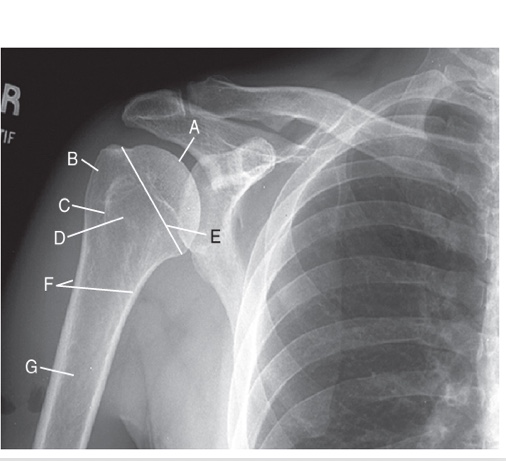

head of humerus

A

greater tubercle

B

intertubercle sulcus

C

lesser tubercle

D

anatomic neck

E

surgical neck

F

body

G